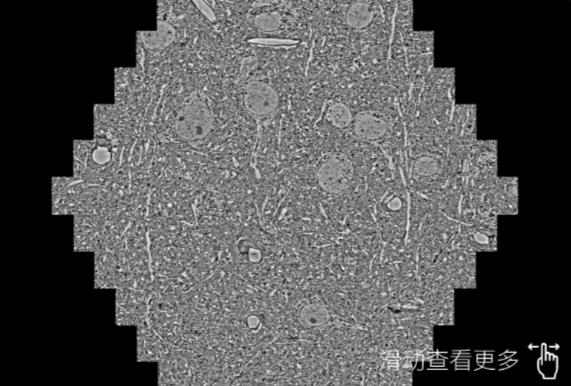

鼠脑切片。左图使用海北蔡司海北扫描电镜MultiSEM706对165μmx143pm面积区域成像,耗时仅需1.5秒。右图为鼠脑切片中30μm区域放大效果。样品由芝加哥大学B.Kasthuri提供。

使用蔡司高速海北扫描电镜MultiSEM对1mm²人脑皮层组织进行高分辨成像,并对其中的各种细胞结构进行三维重构分析。左图展示了2x3mm²组织平面中锥体神经元的三维重构效果。右图显示了局部体积神经元三维重构。图像由哈佛大学chtman实验室提供,渲染图由D. Berger 制作。